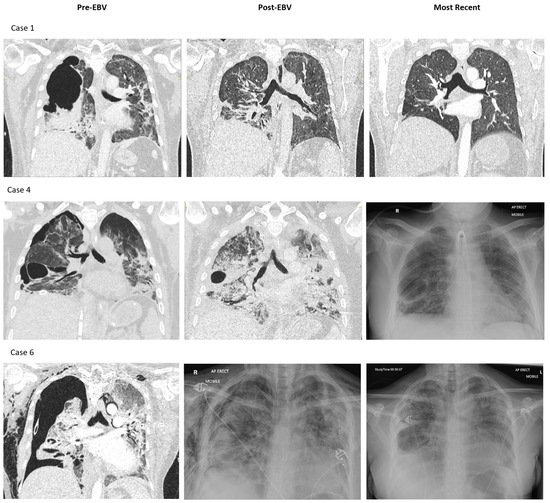

3.3. Imaging and Patient Outcomes